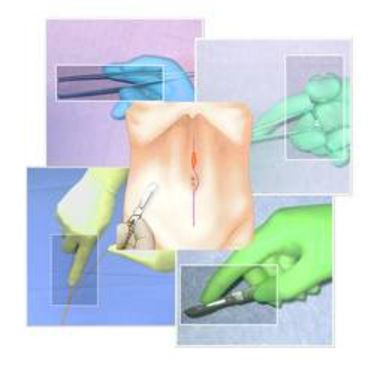

BASIC SURGICAL SKILLS

BASIC SURGICAL SKILLS

BASIC SURGICAL SKILLS

BASIC SURGICAL SKILLS

BASIC SURGICAL SKILLS

BASIC SURGICAL SKILLS